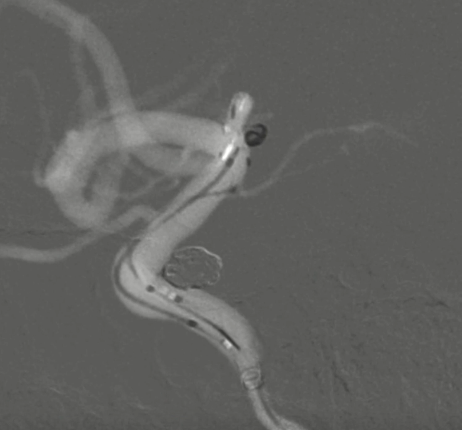

工作位侧位造影(图片)

工作位侧位造影(视频)

术前外院 DSA 2025-02

箭头所指右侧A1微小动脉瘤